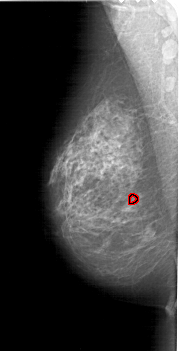

A_1632_1.RIGHT_MLO

RIGHT_MLO LINES 6646 PIXELS_PER_LINE 3181 BITS_PER_PIXEL 12 RESOLUTION 43.5 NON_OVERLAY

FILE: A_1632_1.LEFT_MLO.OVERLAY

TOTAL_ABNORMALITIES 1

ABNORMALITY 1

LESION_TYPE CALCIFICATION TYPE PLEOMORPHIC DISTRIBUTION CLUSTERED

ASSESSMENT 4

SUBTLETY 2

PATHOLOGY BENIGN

TOTAL_OUTLINES 1